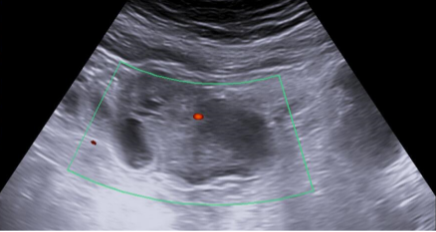

Compresión extrínseca de la vejiga por tumoración mixta solidoquística que proceden de zona anexial derecha, en zona superior y lateral derecha.

La ecografía abdominal es una herramienta muy útil para el Médico de Familia y permite adelantar el tiempo diagnóstico y el inicio del tratamiento de la patología subyacente. En este caso, gracias a la realización de una ecografía clínica en el centro de salud, se pudo objetivar una masa anexial derecha, causante de la sintomatología, y de esta forma iniciar el tratamiento de una forma precoz.